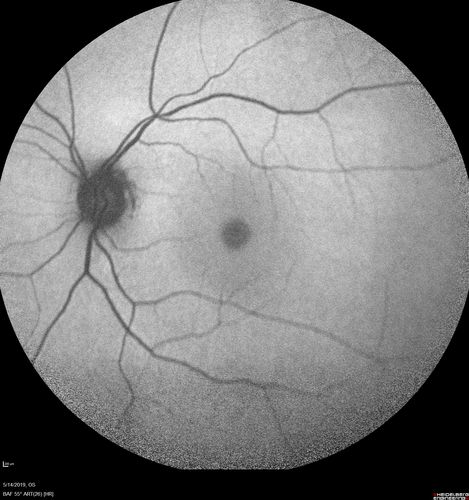

Macroaneurysm - Macular Hemorrhage - Branch Retinal Aterial Occlusion

62 year old African American female with chronic hypertension and vision loss for 2 weeks. VA is 20/400

Macroaneurym - Fresh Macular Hemorrhage - branch retinal arterial occulsion distal to MA